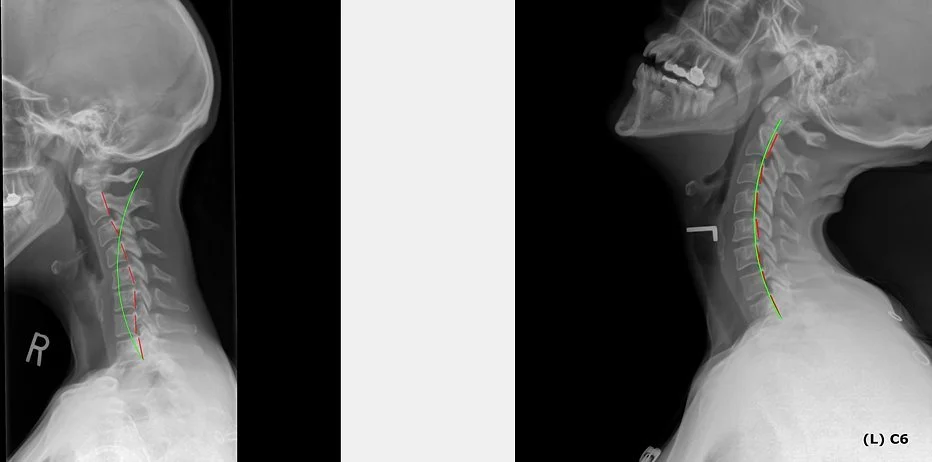

On the LEFT is a patient who presented with a reversal of their neck curve. This has been associated with many symptoms including headaches, pain, weakness, and numbness. It is also been shown to lead to early spinal degeneration and arthritis.

On the RIGHT is the same patient fitted on a cervical orthotic. This allows us to determine:

1. Can the center of gravity be corrected?

2. Can the reversed curve be corrected and how much?

3. A treatment goal. How much improvement do we expect to see after the patient is corrected?